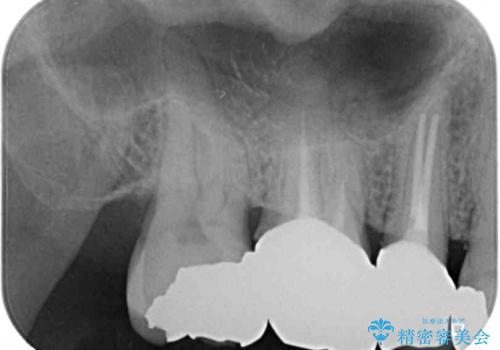

レントゲン写真から、特に大きなむし歯などは認められませんでしたが、根管治療があまり十分に行われているとは言えない状態でした。

まずは仮歯を装着し、根管治療を行った上で土台を植立し、オールセラミッククラウンにて補綴治療を行うこととしました。